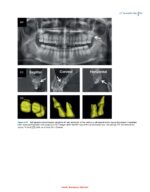

TADs allow for more predictable and effective treatment outcomes, such as correcting gummy smiles, reinforcing molar anchorage, and achieving complex tooth movements that were previously considered impossible—like managing deeply impacted mandibular molars. As a result, TADs have significantly expanded the envelope of orthodontic tooth movement.